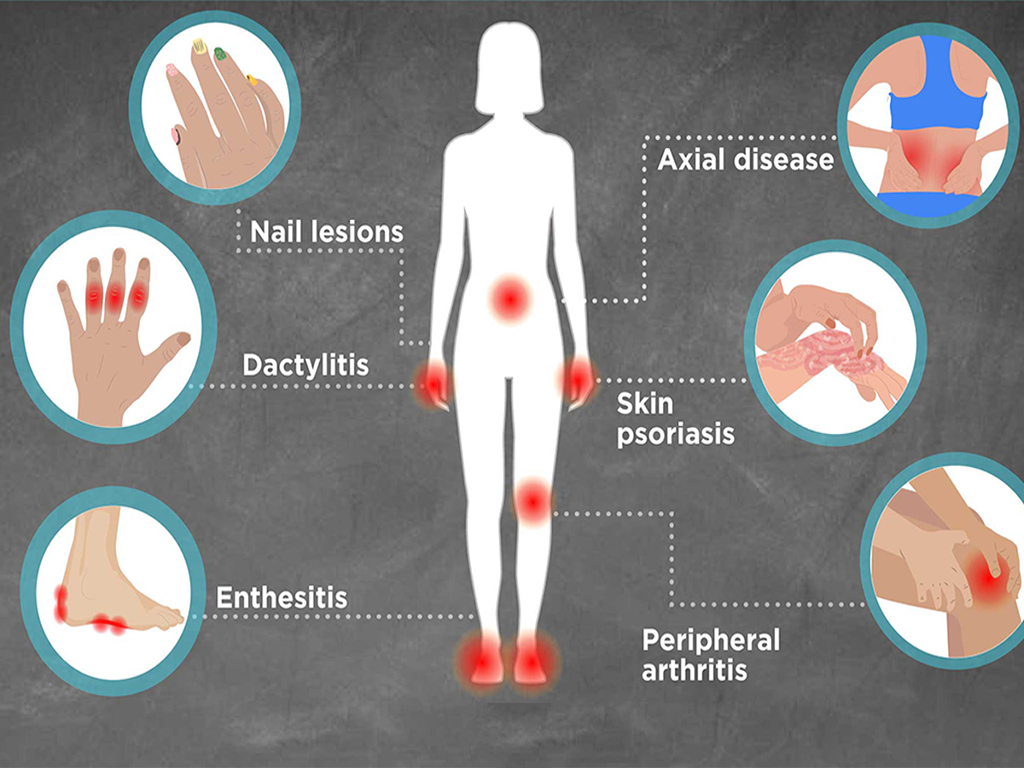

Arthritis is a general term used to describe a group of conditions that cause inflammation, pain, stiffness, and reduced mobility in one or more joints. It affects people of all age groups and can range from mild discomfort to severe disability if not managed properly.

There are over 100 types of arthritis, but the most common are Osteoarthritis (OA) and Rheumatoid Arthritis (RA).

Persistent joint pain and tenderness

Swelling around affected joints

Stiffness, especially in the morning or after inactivity

Redness and warmth over the joint

Difficulty performing daily activities

In severe cases, joint deformity